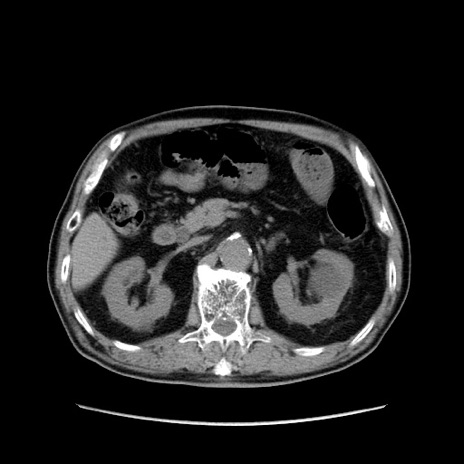

症例24(横断像)

【症例】80歳代男性

【主訴】左側腹部痛、嘔吐

【現病歴】本日早朝より左腹部に痛みあり。昼頃嘔吐認めたため、救急要請。

【既往歴】直腸癌(Mile手術)、胆摘

【身体所見】意識清明、BT 35.9℃、BP 221/93mmHg、SpO2 97%(RA) 、腹部:左ストーマ周囲に限局性の腹部膨隆あり。 膨隆部自発痛・圧痛あり・軟。

【データ】WBC 7700、CRP 0.09